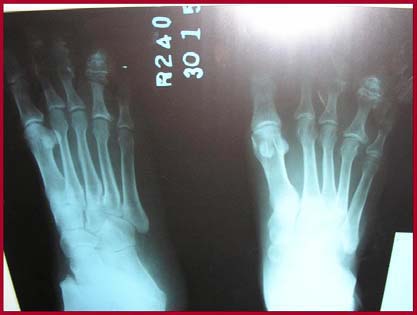

Radiological examination revealed that there were expansion and deformity of right 3rd and 4th toe with osteophytosis.

Fig-2. X-Ray of the Foot